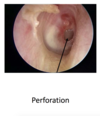

Complications of Acute Otitis Media

Tympanic membrane perforation , tympanosclerosis

Cholesteatoma pathophysiology & causes

form from eustashian tube dysfunction> “-“pressure in middle ear> the weakest part of eardrum starts to sink in> the squamous epitheliam on the outer surf of the eardrum (typmpani cmemebrane) starts to grow in the middle ear and form a sac or cyst of cells

- Secondary acquired – insult to tympanic membrane, such as perforation secondary to otitis media, trauma or surgical manipulation of the ear drum